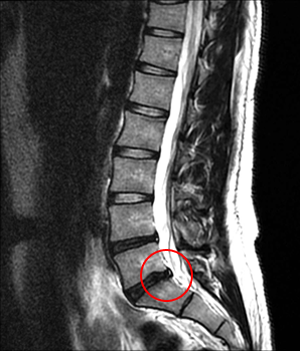

<Ç㸮µð½ºÅ© ȯÀÚ MRI>

Ç㸮µð½ºÅ©¶õ 33°³ ôÃß Áß °æÃß 1~7¹ø, ¿äÃß 1~6¹ø ,ÈäÃß 1~12¹ø ÀÌ Ãß°£ÆÇÀÌ Á¦ÀÚ¸®¸¦ ¹þ¾î³ª

ÁÖº¯ ½Å°æÀ» ¾Ð¹ÚÇÏ¿© ÅëÁõ ¹× ±âŸ ÀÌ»óÀÌ ¹ß»ýÇÏ´Â °ÍÀ» ¸»ÇÕ´Ï´Ù.